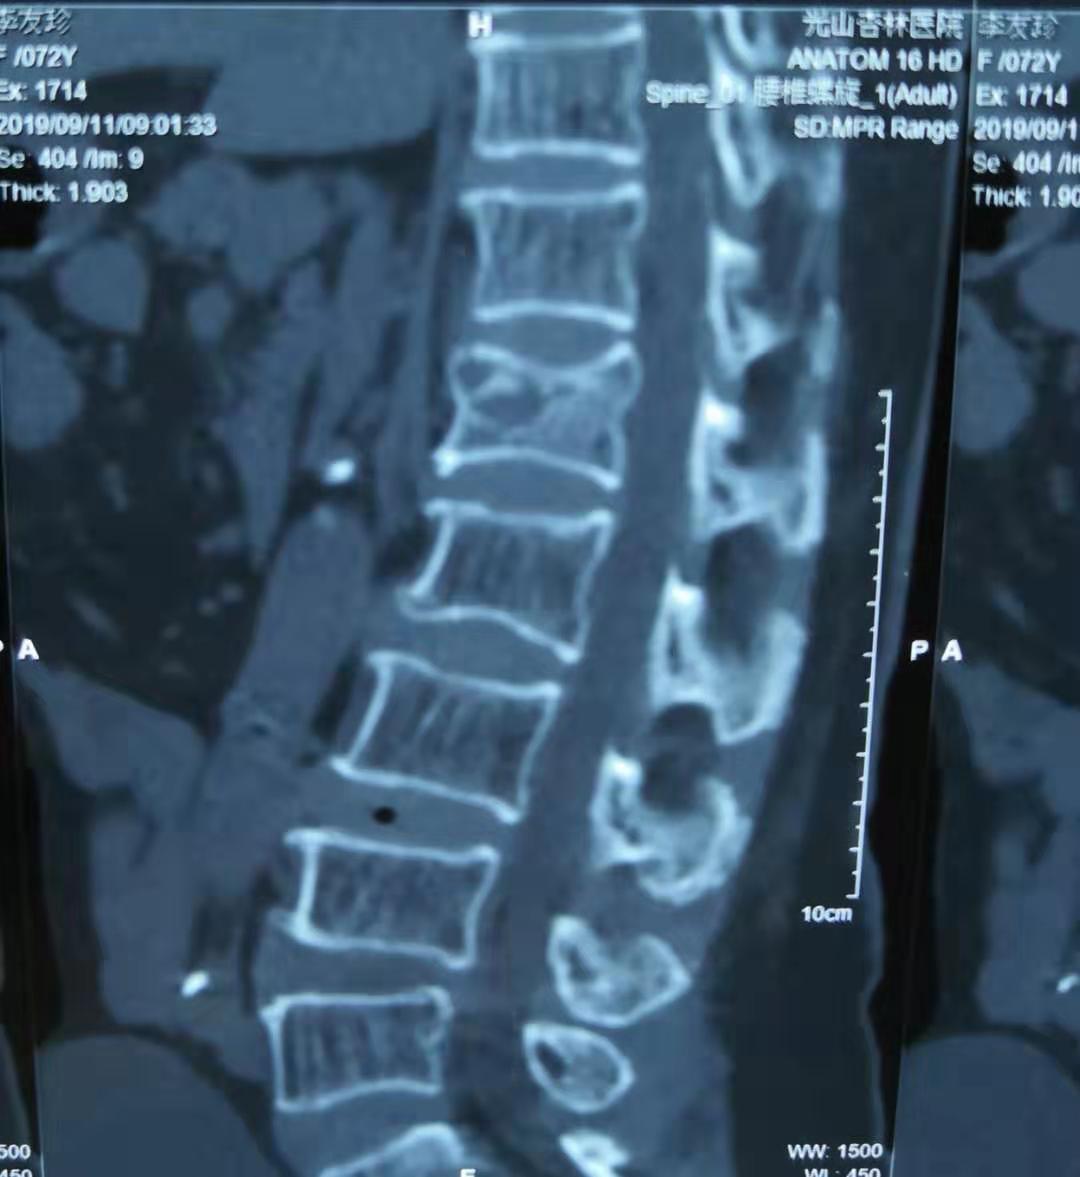

今天医院收到一位腰椎骨折的患者,还伴随有长期腰痛胸痛和消化不良,外院诊断为腰椎单纯骨折并胸部巨大脂肪瘤。在我院高档CT、磁共振的检查下,却是另外一种发现。

我们的设备,清楚地显示出外院照片没有发现的细节。

单纯腰椎骨折的背后,还发现了一个被压碎的血管瘤。而且其余椎体还有几个小的血管瘤。这就不是单纯骨折,而是病理性骨折。符合患者在轻微运动下就发生骨折的事实。